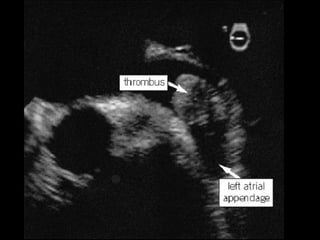

Hemodynamic Changes in LAA with AF

AFSinus Rhythm

Mean peak velocity 52 cm/s Mean peak velocity 26 cm/s

Clot in the LAA on MRI Clot in the LAA on Echo Thrombus

LAA Emptying Flow Velocity Echo Signals

With AF, LAA blood flow velocity decreases, increasing risk of thrombus formation